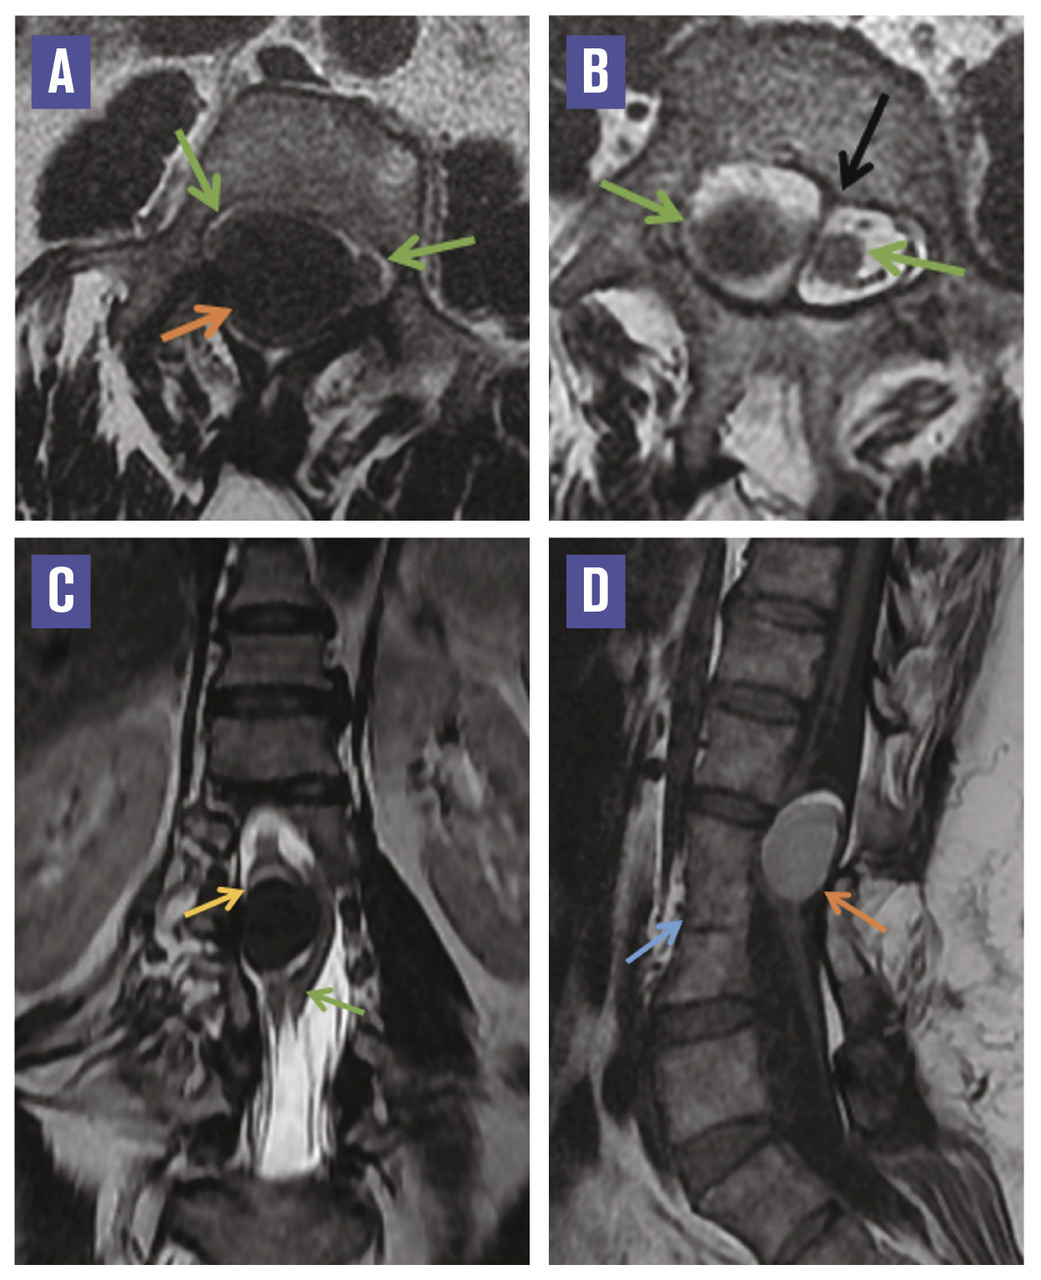

L’imagerie par résonance magnétique mettait en évidence une moelle bas attachée, avec deux hémimoelles lombaires séparées par un éperon fibreux, en regard de L1, associée à un bloc vertébral L2-L3-L4 et à une formation intradurale extramédullaire à la hauteur de L2-L3, refoulant l’hémimoelle droite, bien limitée, en hypersignal T1, hyposignal T2 franc, sans rehaussement après injection de gadolinium. L’ensemble évoquait une diastématomyélie de type II associée à un kyste neurentérique à contenu protéique ou hématique (figure ).

La diastématomyélie est un dysraphisme spinal fermé rare, caractérisé par une division de la moelle épinière en deux cordons, qui s’accompagne souvent d’un éperon osseux ou cartilagineux scindant la moelle.1 Souvent lombaire, elle prédomine chez la femme et se révèle habituellement chez de jeunes patients, rarement à l’âge adulte. Les circonstances de découverte sont variables : douleurs, troubles sensitivomoteurs ou de la sphère génito-urinaire (urgences mictionnelles, incontinence).1 L’imagerie par résonance magnétique (IRM) est l’examen de référence pour étudier le rachis malformatif et analyser le cordon médullaire.

Les kystes neurentériques se développent quant à eux à partir de reliquats de l’endoderme en position ectopique dans le canal rachidien. Ils sont intraduraux, extramédullaires, et se situent au niveau de la jonction cervicothoracique ou du cône terminal. En IRM, ils se présentent comme des structures arrondies de la moelle antérieure, de même signal que le LCR, ou iso-intenses à la moelle en cas de contenu protéique, sans rehaussement après injection de gadolinium. Ces lésions peuvent s’associer à des anomalies vertébrales de type spina-bifida, fusion intervertébrale, diastématomyélie ou à un simple élargissement du canal rachidien.2